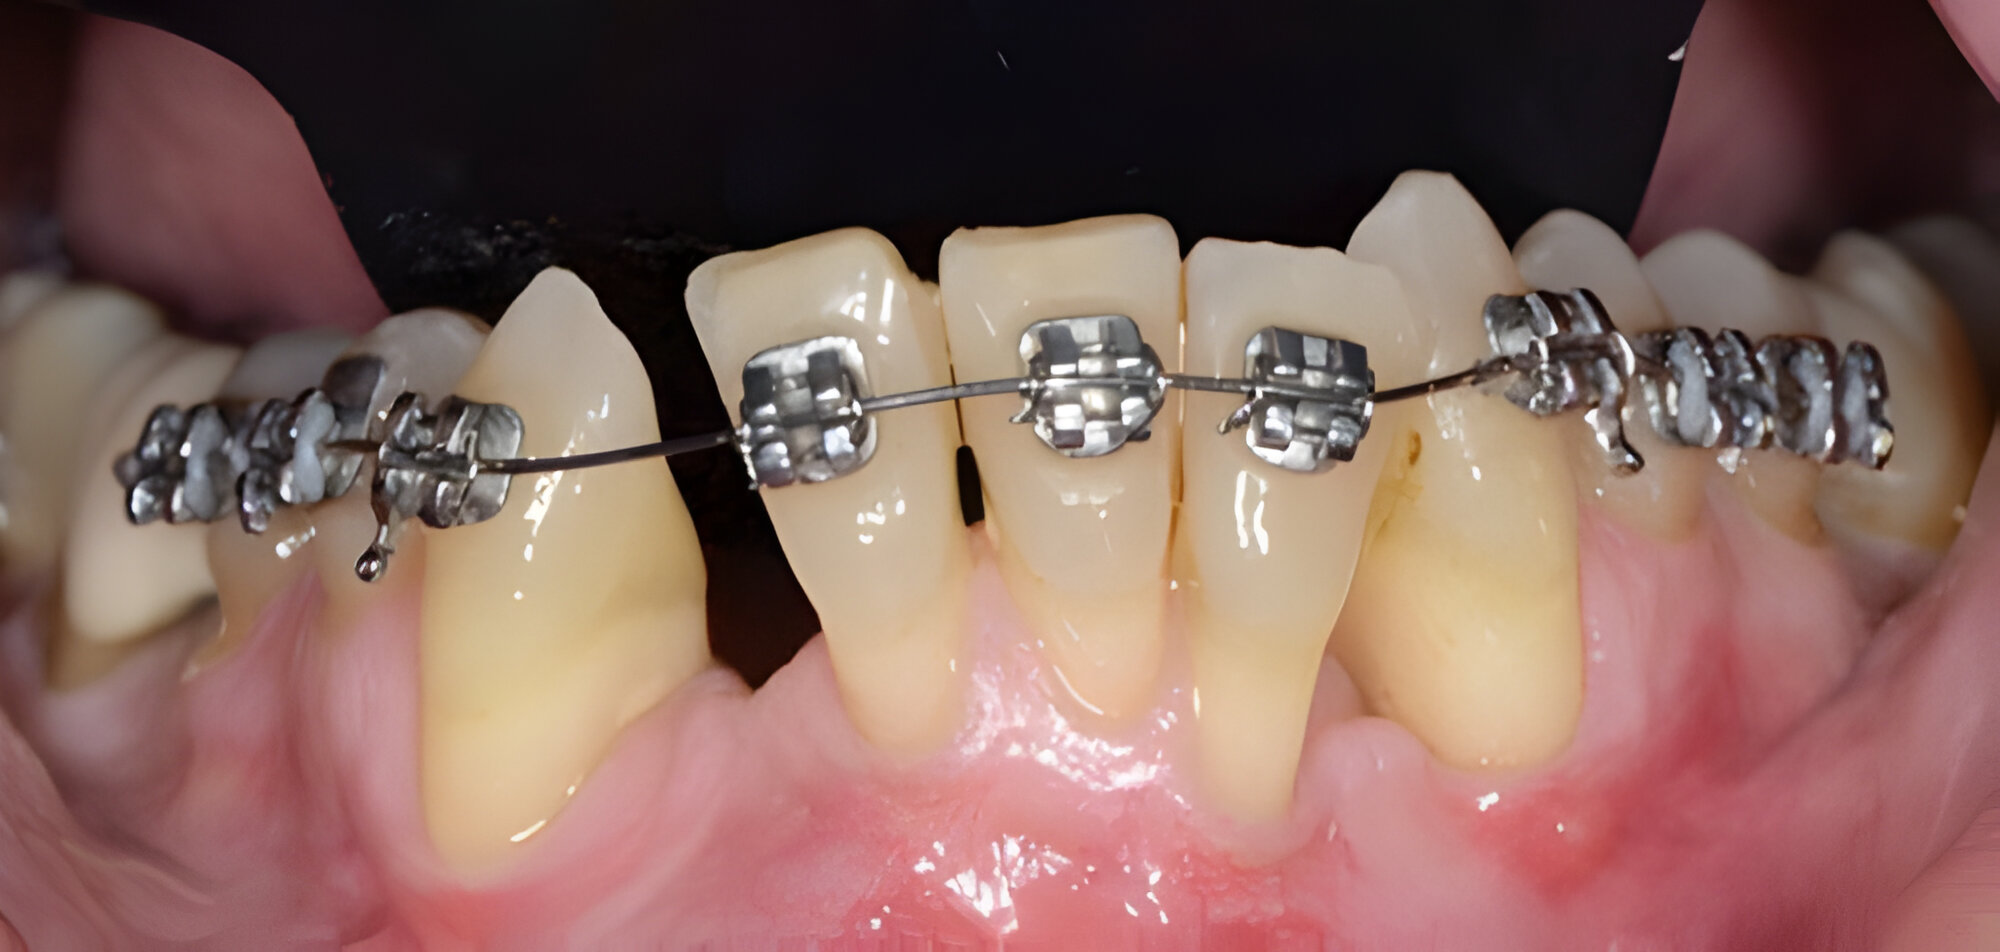

Lung lay răng khi niềng trở nên bất thường khi răng có độ lung lay vượt mức sinh lý. Răng có thể di động theo chiều ngang >1mm hoặc có dấu hiệu lún/trồi theo chiều dọc. Về mặt lâm sàng, đây là hệ quả của việc lực chỉnh nha quá mạnh vượt ngưỡng chịu đựng của tổ chức quanh răng, dẫn đến sang chấn khớp cắn hoặc tiêu xương ổ răng vượt quá 20 - 30% chiều dài chân răng. Các dấu hiệu cảnh báo đi kèm bao gồm túi nha chu sâu hơn 3mm, nướu sưng đỏ dai dẳng, hoặc cảm giác đau buốt kéo dài trên 7 ngày không thuyên giảm.

Nguyên nhân có thể do kỹ thuật kiểm soát lực chưa chuẩn xác hoặc do viêm nha chu tiến triển làm phá hủy hệ thống nâng đỡ răng. Để đảm bảo an toàn, khi xuất hiện các triệu chứng cực đoan này, bác sĩ cần chụp phim X-quang cận chóp để đánh giá mật độ xương và điều chỉnh lại hệ thống lực kéo ngay lập tức.